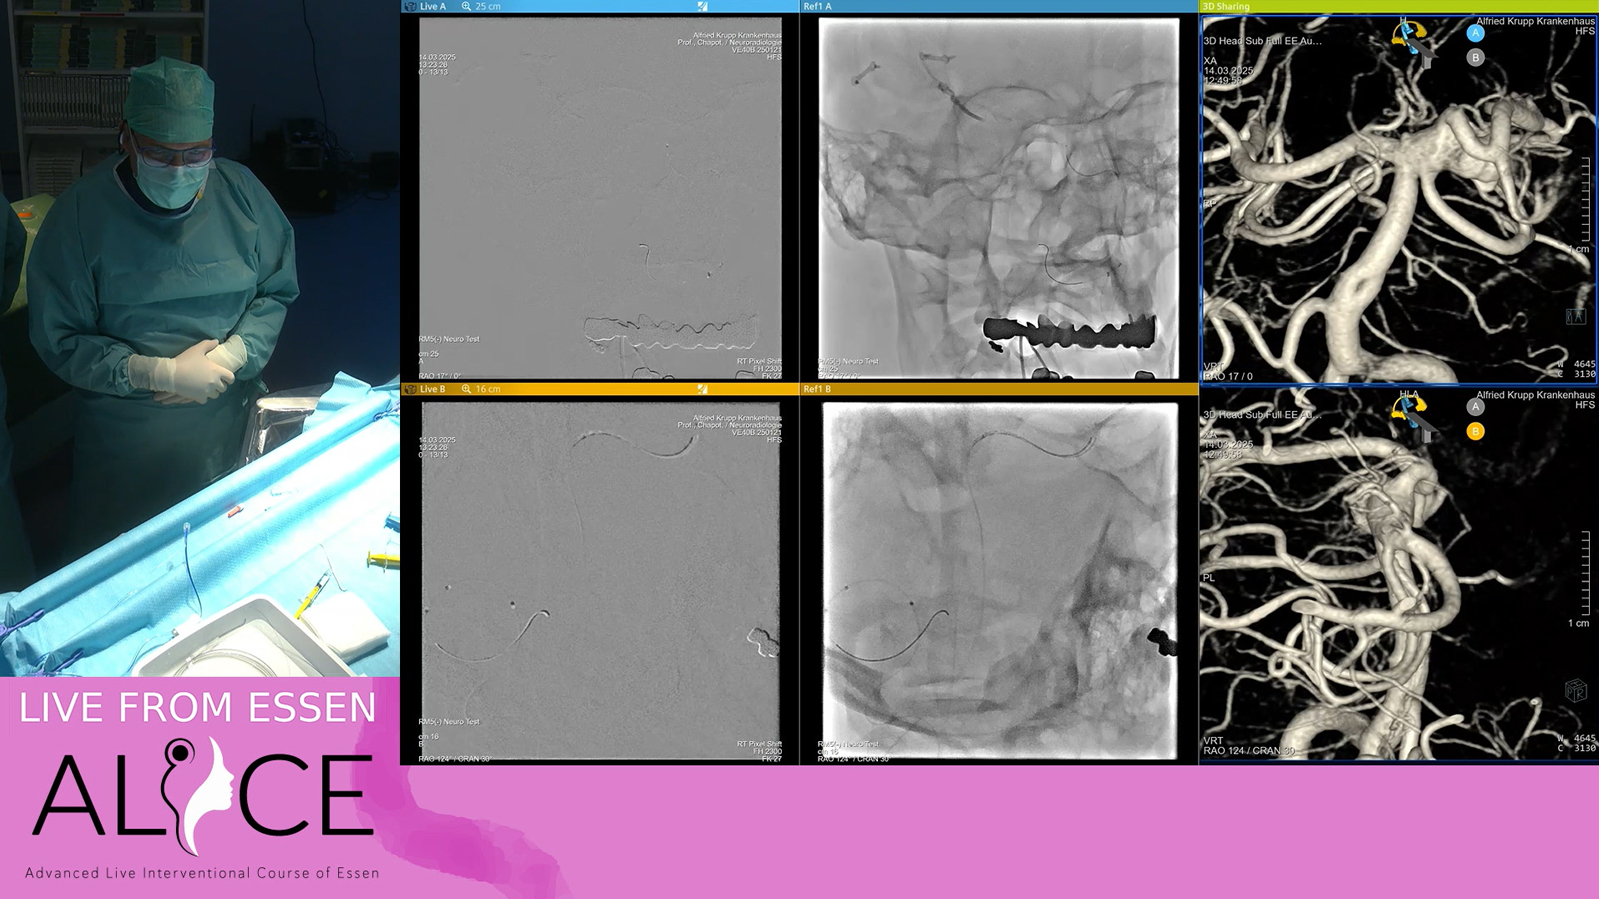

Small basilar tip aneurysm treated by kissing balloons and coils and followed by V stenting